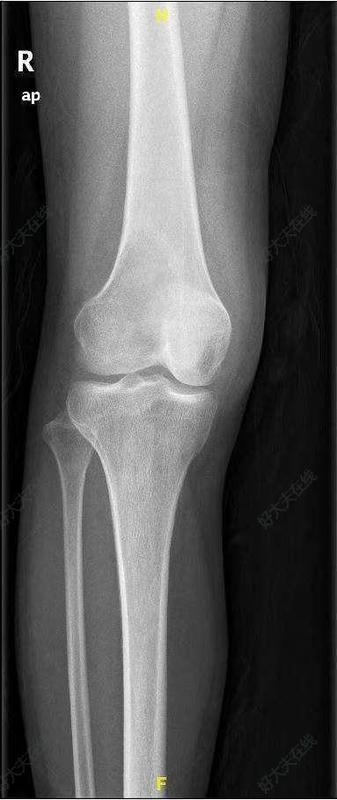

一、什么是骨腫瘤,常見的病理類型有哪些?骨腫瘤是指生長于骨組織的任何異常生長的腫物,可分為良性或惡性(肉瘤)。常見原發(fā)惡性骨腫瘤包括骨肉瘤、尤文肉瘤、軟骨肉瘤等。而乳腺癌、肺癌、前列腺癌、腎癌等為常見的骨轉(zhuǎn)移癌類型。常見的良性腫瘤包括骨軟骨瘤、內(nèi)生軟骨瘤、骨樣骨瘤、骨囊腫、骨纖維結(jié)構(gòu)不良、嗜酸性細(xì)胞肉芽腫等。還有一些腫瘤介于良惡性交界,如骨巨細(xì)胞瘤等。①骨肉瘤骨肉瘤是最常見的原發(fā)惡性骨腫瘤,統(tǒng)計(jì)發(fā)病率為4-5/百萬。傳統(tǒng)骨肉瘤好發(fā)于青少年,最常發(fā)生在10-20歲階段,60%發(fā)生在25歲以下。男性好發(fā),與女性的發(fā)病率的比值為3:2。傳統(tǒng)骨肉瘤好發(fā)于四肢長骨,尤其是股骨遠(yuǎn)端、脛骨近端和肱骨近端。骨肉瘤最常見的臨床表現(xiàn)是疼痛和腫塊。疼痛可放射至臨近關(guān)節(jié),初期疼痛多為間斷性隱痛,隨病情發(fā)展疼痛逐漸加重,多發(fā)展為持續(xù)性疼痛,休息、制動或者一般止痛藥無法緩解。早期癥狀可能會時輕時重,因此很難診斷;隨著疾病進(jìn)展,癥狀會持續(xù)加重。腫瘤內(nèi)大多數(shù)細(xì)胞的分化方向決定了骨肉瘤的影像學(xué)表現(xiàn),可呈骨樣、軟骨樣、成纖維樣或者纖維組織樣,伴有不同程度的反應(yīng)骨形成。影像學(xué)上一些骨肉瘤成骨明顯;另一些則以溶骨性破壞為主。當(dāng)腫瘤穿破骨皮質(zhì),侵入到軟組織內(nèi)時,可出現(xiàn)最具特征的影像學(xué)改變,即特征性骨膜反應(yīng)。骨肉瘤的另一個常見影像學(xué)表現(xiàn)是不規(guī)則鈣化或骨外軟組織包塊內(nèi)的骨化。CT掃描和MRI在術(shù)前有助于判斷腫瘤的范圍,這對確定一些患者是否能夠保肢有極為重要的作用。放射性核素骨掃描成像可用于檢測病變的活動性,確定是否存在多發(fā)的病變或骨轉(zhuǎn)移,但特異性不高,不能單獨(dú)作為診斷依據(jù)。PET-CT檢查是最近幾年興起的先進(jìn)全身篩查技術(shù),能對腫瘤進(jìn)行早期診斷和鑒別診斷,鑒別腫瘤有無復(fù)發(fā),對腫瘤進(jìn)行分期和再分期,尋找腫瘤原發(fā)和轉(zhuǎn)移灶,指導(dǎo)和確定腫瘤的治療方案、評價療效。除經(jīng)典骨肉瘤之外,臨床上還有毛細(xì)血管擴(kuò)張型骨肉瘤、髓內(nèi)高分化(低惡髓內(nèi)型)骨肉瘤、小細(xì)胞性骨肉瘤、多中心骨肉瘤、骨旁骨肉瘤、骨膜骨肉瘤、高度惡性骨表面骨肉瘤等多種類型的骨肉瘤。②軟骨肉瘤軟骨肉瘤是一種軟骨來源的惡性腫瘤,好發(fā)于成年人和老年人。大多數(shù)患者年齡大于50歲,發(fā)病高峰在40-70歲間。男性稍常見。單獨(dú)或是同時存在的局部腫脹和疼痛,都是重要的癥狀。這些癥狀很常見,并且持續(xù)時間一般較長。常見部位是骨盆(髂骨最常受累),隨后是在股骨近端,肱骨近端,股骨遠(yuǎn)端和肋骨。原發(fā)軟骨肉瘤很少見于手足部的短骨(占所有軟骨肉瘤的1%)。影像學(xué)檢查對于診斷軟骨腫瘤有重要的作用。發(fā)生在骨盆的原發(fā)軟骨肉瘤呈現(xiàn)梭形膨脹,伴有皮質(zhì)骨增厚。表現(xiàn)為散在分布的點(diǎn)狀射線透明區(qū)和環(huán)樣不透明(礦化)區(qū)。皮質(zhì)骨侵蝕和破壞較常見,皮質(zhì)骨通常增厚但是可能缺乏或是不存在骨膜反應(yīng)。MRI有助于描繪腫瘤的范圍和明確軟組織受累情況。CT掃描可提示基質(zhì)鈣化。軟骨肉瘤是軟骨分化的惡性腫瘤,病理上依據(jù)腫瘤的惡性程度而表現(xiàn)不同:低度惡性的軟骨肉瘤需結(jié)合臨床表現(xiàn)、X線特征來診斷??筛鶕?jù)細(xì)胞數(shù)量和細(xì)胞學(xué)表現(xiàn)將軟骨肉瘤分為I級、II級、III級三個級別,惡性程度由低到高?;顧z是術(shù)前明確診斷的一種輔助檢查方法,軟骨肉瘤的治療首選手術(shù)切除。多數(shù)軟骨肉瘤分化較好,但是切除不徹底時非常容易局部復(fù)發(fā)。腫瘤生長緩慢,可向周圍軟組織伸展,但是轉(zhuǎn)移少見,并且多發(fā)生在晚期。轉(zhuǎn)移的病例一般為高度惡性。最常見的轉(zhuǎn)移部位為肺臟,其他的少見部位包括肝、腎、淋巴結(jié)、骨轉(zhuǎn)移等。軟骨肉瘤對傳統(tǒng)放療不敏感。但近年,隨著放療技術(shù)的進(jìn)步,質(zhì)子放療等方法可以在一定程度上控制腫瘤?;煹膱?bào)道少見。對于去分化的軟骨肉瘤,可考慮進(jìn)行化療治療。去分化軟骨肉瘤是一類特殊的軟骨肉瘤,約占全部軟骨肉瘤的10%。平均發(fā)病年齡為50-60歲,年齡范圍為29-85歲。腫瘤通常為惡性溶骨性骨內(nèi)病變,易發(fā)生皮質(zhì)骨穿孔和骨外侵蝕。骨盆是其好發(fā)的部位之一。去分化軟骨肉瘤是侵蝕性腫瘤,該腫瘤有比較高的惡性程度,預(yù)后普遍比較差。5年生存率低于25%。盡管進(jìn)行了針對侵襲性腫瘤的治療,仍有大約90%的患者死亡,并在兩年內(nèi)有明確的轉(zhuǎn)移。繼發(fā)性軟骨肉瘤是繼發(fā)于良性前驅(qū)腫瘤如骨軟骨瘤和內(nèi)生軟骨瘤的一種軟骨肉瘤。繼發(fā)性外周性軟骨肉瘤的發(fā)病年齡多為20-40歲。最常見的部位是骨盆,尤其是髂骨,其次為股骨和肱骨近端、肩胛骨。多數(shù)繼發(fā)性軟骨肉瘤為低度惡性,預(yù)后較好。繼發(fā)于內(nèi)生軟骨瘤病的軟骨肉瘤有和傳統(tǒng)軟骨肉瘤相同的預(yù)后,都有賴于腫瘤的部位和分級。間葉型軟骨肉瘤是一種罕見的惡性腫瘤,占全部原發(fā)軟骨肉瘤的3%-10%。盡管可以發(fā)生在任何年齡,但是發(fā)病率高峰是在10歲—30歲。它是由高分化透明軟骨島與未分化原始間葉細(xì)胞組成的惡性腫瘤,約占軟骨肉瘤的3%。骨盆是其最好發(fā)的部位之一。間葉型軟骨肉瘤是一種高惡性度腫瘤,有局部復(fù)發(fā)和遠(yuǎn)處轉(zhuǎn)移的傾向。根治性腫瘤切除可能是比較好的治療方法。有研究顯示它對化療和放療敏感,這可能是由于腫瘤中的高度細(xì)胞化的未分化區(qū)域?qū)Ψ暖熀突熋舾小"塾任娜饬?原始神經(jīng)外胚瘤尤文肉瘤(Ewing肉瘤)/原始神經(jīng)外胚瘤并不常見,約占原發(fā)惡性骨腫瘤的6-8%,少于骨髓瘤、骨肉瘤、軟骨肉瘤。但它是兒童常見骨骼和軟組織肉瘤的第二位。尤文肉瘤/原始神經(jīng)外胚層腫瘤好發(fā)于男性,男女比例約為1.4:1。將近80%的患者小于20歲,而發(fā)病高峰年齡為10-20歲,大于30歲的患者很少見。尤文肉瘤/原始神經(jīng)外胚瘤好發(fā)于長骨的骨干和干骺端,骨盆和肋骨也是常見的累及部位。局部的疼痛是最常見的臨床癥狀,同時伴有局部腫脹或觸及腫塊。對患者進(jìn)行全身檢查時經(jīng)常發(fā)現(xiàn)發(fā)熱、貧血、白細(xì)胞增多和血沉增快等表現(xiàn)。影像學(xué)上,一個發(fā)生于長骨或扁平骨骨干上的邊界不清的溶骨性病灶是最常見的特征,而滲透性或蟲蝕樣骨破壞伴洋蔥樣多層骨膜反應(yīng)也是其特征之一,腫瘤的皮質(zhì)也可以厚薄不均。尤文肉瘤常表現(xiàn)為一個巨大的、邊界不清的腫物,骨膨脹性破壞也可以見到。MRI和CT檢查可以幫助評價腫瘤在骨骼和軟組織中的擴(kuò)張情況。尤文肉瘤在影像學(xué)上應(yīng)與骨肉瘤、骨髓炎、嗜酸性肉芽腫等疾病鑒別,但這些可以通過病理檢查解決。①骨巨細(xì)胞瘤骨巨細(xì)胞瘤不屬惡性腫瘤,但具有局部侵襲性、并有遠(yuǎn)處轉(zhuǎn)移潛能的交界性腫瘤。占骨所有原發(fā)性腫瘤4-5%。骨巨細(xì)胞瘤發(fā)生在已經(jīng)骨骼發(fā)育成熟的患者中,20歲到40歲之間高發(fā)(61%)。盡管有10-15%的病例發(fā)生于二十歲以內(nèi),但未成年人極少患骨巨細(xì)胞瘤,10歲以下的兒童更是極為罕見。女性患者略多。骨巨細(xì)胞瘤是一種最有爭議的骨腫瘤。在大約20%—40%的病例中,骨巨細(xì)胞瘤具有持續(xù)進(jìn)展的潛在惡性,約5%—10%病例會出現(xiàn)肉瘤惡變,甚至局部還沒有出現(xiàn)明顯惡變就已發(fā)生遠(yuǎn)處轉(zhuǎn)移。骨巨細(xì)胞瘤患者典型的臨床表現(xiàn)有疼痛,腫脹,經(jīng)常性的關(guān)節(jié)活動受限。5-10%的患者可以出現(xiàn)病理性骨折。持續(xù)加重的劇痛為最常發(fā)生的也是首發(fā)的癥狀,并伴隨局部腫脹和壓痛。骨巨細(xì)胞瘤血供十分豐富,常存在小的鮮紅色或是棕色的囊腔。即使是侵襲性較高的骨巨細(xì)胞瘤也很少穿破關(guān)節(jié)軟骨。膨脹的薄層皮質(zhì)骨經(jīng)常發(fā)生穿孔或是部分破壞(影像學(xué)表現(xiàn)為“侵襲性”病灶),但這并不代表腫瘤就是惡性的。由于腫瘤和干骺端的松質(zhì)骨之間沒有明顯的界限,這是骨巨細(xì)胞瘤在刮除術(shù)后經(jīng)常復(fù)發(fā)的原因所在。如果腫瘤細(xì)胞同時呈異形性,則不排除腫瘤細(xì)胞發(fā)生惡變的可能。骨巨細(xì)胞瘤具有局部侵襲性,偶然能發(fā)生遠(yuǎn)處轉(zhuǎn)移。組織學(xué)上的特點(diǎn)并不能預(yù)示其局部侵襲性的程度。通過刮除術(shù)、植骨法、骨水泥填充、冷凍療法或石炭酸燒灼治療,局部復(fù)發(fā)率大約有20%。通常復(fù)發(fā)發(fā)生在兩年之內(nèi)。2%的骨巨細(xì)胞瘤可出現(xiàn)肺轉(zhuǎn)移。肺轉(zhuǎn)移平均在原發(fā)瘤診斷后的3-4年內(nèi),轉(zhuǎn)移瘤可以是單灶性也可是多灶性的。部分轉(zhuǎn)移瘤生長非常緩慢,甚至有些能自發(fā)消退;部分腫瘤是進(jìn)展性的,最終可以導(dǎo)致患者的死亡。①骨軟骨瘤骨軟骨瘤是一種常見的、軟骨源性的良性腫瘤,是位于骨表面的骨性突起物,又稱為外生骨疣,為最常見的良性骨腫瘤。多發(fā)生于青少年,隨機(jī)體發(fā)育而增大,當(dāng)骨骺線閉合后,其生長也停止。多見于長骨干骺端,如股骨遠(yuǎn)端、脛骨近端和肱骨近端??煞譃閱伟l(fā)與多發(fā)性骨軟骨瘤兩種,單發(fā)占85%。骨軟骨瘤的確切病因尚不明確,一般認(rèn)為與遺傳、生長激素刺激、局部微環(huán)境改變等因素有關(guān)。骨軟骨瘤X線表現(xiàn)為單發(fā)或多發(fā),在干骺端可見從皮質(zhì)突向軟組織的骨性突起,逆向關(guān)節(jié)生長,其皮質(zhì)和松質(zhì)骨以窄小或?qū)拸V的蒂與正常骨相連,彼此髓腔相通,皮質(zhì)相連續(xù),突起表面為軟骨帽,不顯影,厚薄不一,有時可呈不規(guī)則鈣化影。骨軟骨瘤發(fā)生惡性變可出現(xiàn)疼痛、腫脹、軟組織包塊等癥狀;X線平片可見原來穩(wěn)定的骨軟骨瘤再度生長,骨質(zhì)破壞,呈現(xiàn)云霧狀改變以及鈣化不規(guī)則等表現(xiàn)。CT、MRI可進(jìn)一步明確腫瘤性質(zhì)及累及范圍。骨軟骨瘤因有典型的臨床表現(xiàn)及影像學(xué)特征,診斷容易,不易與其他腫瘤混淆,但需要排除多發(fā)性骨軟骨瘤的可能。多發(fā)性骨軟骨瘤常伴有家族遺傳病史,且以膝關(guān)節(jié)周圍多見,對稱性明顯,易鑒別。一般不需治療,密切觀察。若腫瘤生長過快,有疼痛或影響關(guān)節(jié)活動功能;影響鄰骨或發(fā)生關(guān)節(jié)畸形;壓迫神經(jīng)、血管以及腫瘤自身發(fā)生骨折;腫瘤表面滑囊炎或病變活躍懷疑有惡變可能者應(yīng)行切除術(shù)。切除應(yīng)從腫瘤基底四周部分正常骨組織開始,包括纖維膜或滑囊、軟骨帽等,以免復(fù)發(fā)。單發(fā)骨軟骨瘤惡變率低于1%,惡變者應(yīng)行擴(kuò)大廣泛切除。②內(nèi)生軟骨瘤內(nèi)生軟骨瘤是第二位常見的良性骨腫瘤,是一種透明軟骨組織構(gòu)成的、軟骨源性的良性腫瘤,好發(fā)于手和足的管狀骨,其次為長骨骨干。發(fā)病年齡多在20~40歲,手足部位的短管狀骨為好發(fā)部位,其次為股骨、肱骨、脛骨和肋骨。腫瘤生長緩慢,體積小,幾乎無血管,病變多無明顯癥狀,往往因?yàn)槔^發(fā)病理性骨折而被偶然發(fā)現(xiàn)。許多病例是在檢查創(chuàng)傷、關(guān)節(jié)病或骨骼肌肉痛時偶然發(fā)現(xiàn)。單發(fā)的內(nèi)生軟骨瘤可能發(fā)生惡變?yōu)檐浌侨饬?,發(fā)生率低于1%,惡變主要發(fā)生在長骨和扁平骨內(nèi)。內(nèi)生軟骨瘤X線表現(xiàn):在短管狀骨,病變多顯示髓腔內(nèi)有橢圓形透亮點(diǎn),呈溶骨性破壞,皮質(zhì)變薄膨脹,溶骨區(qū)內(nèi)有間隔或斑點(diǎn)狀鈣化影,并呈現(xiàn)骨內(nèi)扇貝樣花邊狀改變。而在長骨中,病變可以表現(xiàn)局灶鈣化。CT能準(zhǔn)確地顯示腫瘤基質(zhì)的鈣化情況,常呈煙圈樣或爆米花樣。MRI可進(jìn)一步明確腫瘤髓腔內(nèi)的范圍。內(nèi)生軟骨瘤的治療:對于骨內(nèi)范圍較小的病變,多可保守觀察,非手術(shù)治療。手術(shù)治療適應(yīng)證:①病變范圍較大;②出現(xiàn)明顯癥狀;③存在病理性骨折傾向或已經(jīng)發(fā)生病理性骨折者。手術(shù)方式:病灶刮除并植骨,必要時輔以內(nèi)固定。病灶刮除建議行改良的擴(kuò)大刮除術(shù),病灶刮除后輔以磨鉆、苯酚等物理、化學(xué)方法滅活瘤壁,以減少復(fù)發(fā)。預(yù)后好。③骨樣骨瘤骨樣骨瘤由異常骨樣組織、成骨細(xì)胞組成,其外包繞著反應(yīng)性骨質(zhì)。好發(fā)于青少年,10~20歲最多見,男性多于女性,發(fā)病比率約為2:1。70%~80%的腫瘤病損在長骨,最常見于股骨、脛骨和肱骨的骨干或骨骺端。典型的表現(xiàn)是病人長骨有持續(xù)數(shù)月的鈍痛,夜間加重,服用水楊酸制或非甾體消炎鎮(zhèn)痛藥可緩解。病灶鄰近關(guān)節(jié)時,可表現(xiàn)為關(guān)節(jié)周圍疼痛及滑膜炎癥狀。病變部位淺在時,可表現(xiàn)為局部皮溫升高、腫脹及壓痛。骨樣骨瘤X線表現(xiàn)為骨干皮質(zhì)內(nèi)的病灶,呈現(xiàn)小的圓形或橢圓形的放射透明巢,直徑很少超過1cm,常有致密的硬化骨包繞,邊界清晰。CT對發(fā)現(xiàn)瘤巢最有價值,可顯示一個局限的小的低密度區(qū),周圍包繞著大范圍的高密度反應(yīng)骨的形成。骨樣骨瘤外科治療極為有效。應(yīng)完整切除瘤巢。徹底切除后不會復(fù)發(fā)。適應(yīng)證:①疼痛明顯,持續(xù)時間長;②口服非甾體類消炎鎮(zhèn)痛藥不能緩解者。手術(shù)治療包括病灶切除或微創(chuàng)經(jīng)皮消融術(shù)。手術(shù)切除時對于瘤巢的準(zhǔn)確定位非常關(guān)鍵。經(jīng)皮射頻消融一般在CT引導(dǎo)下完成,創(chuàng)傷小、定位準(zhǔn)確、恢復(fù)快,但有消融不徹底復(fù)發(fā)風(fēng)險。④骨囊腫骨囊腫是好發(fā)于兒童和青少年的長骨干骺端的囊性病變。85%發(fā)病于20歲以下,男女比例2:1。四肢所有骨骼均可發(fā)病,但多見于四肢的長管狀骨(90%在肱骨近端,其次為股骨近端和脛骨近端),通常的發(fā)病部位在長管狀骨的干骺端或靠近生長板處,并且逐漸向骨干移行,大多呈單房性改變,但也有多房者,該病具有自限性和自愈性。病因尚不清楚,被廣泛接受的理論為干骺端重塑時的局灶性缺陷阻斷了組織間液的回流,導(dǎo)致壓力增高,引起局灶性骨壞死并使組織間液聚集。骨囊腫的典型X線表現(xiàn)是中心性的單純?nèi)芄切圆∽?,邊界清楚。病變可膨脹生長,但不穿透皮質(zhì),皮質(zhì)變薄,呈蛋殼樣,無骨膜反應(yīng),除非有病理性骨折。無周圍骨皮質(zhì)破壞和軟組織侵犯。病變可呈單房或者多房,病變長軸與骨干方向一致,病變皮質(zhì)厚薄程度不同,但與正常皮質(zhì)有明顯分界。隨著年齡的增長,囊腫可逐漸向骨干移行。骨囊腫患者年齡很重要,越年輕病變越活躍,手術(shù)治療術(shù)后復(fù)發(fā)的風(fēng)險4倍于年齡較大兒童。該病具有自限性和自愈性,因此非手術(shù)療法起到非常重要的作用。小的無癥狀的上肢病變可以定期拍攝X線片進(jìn)行觀察。較大的病變,如有病理性骨折風(fēng)險,或有癥狀的病變和下肢的病變通常采用刮除術(shù)(可采用或不采用骨移植或內(nèi)固定)治療,或者采用抽吸注射法(常用皮質(zhì)類固醇、骨髓抽出物、脫鈣骨基質(zhì)或其他材料)。因骨折可以引起囊腔愈合,所以上肢的單房性骨囊腫可采用非手術(shù)治療。股骨近端的單房性骨囊腫應(yīng)采用刮除、骨移植和內(nèi)固定聯(lián)合治療。⑤骨纖維結(jié)構(gòu)不良骨纖維結(jié)構(gòu)不良是一種良性病變,骨纖維異樣增殖癥病因不明,與骨先天性發(fā)育異常、骨形成障礙、內(nèi)分泌異常有關(guān)。骨纖維異樣增殖癥多在10歲左右發(fā)病,常在青年期就診,伴內(nèi)分泌紊亂者可在3~4歲發(fā)病,甚至在出生后即有癥狀。本病可發(fā)生在任何骨骼,四肢單發(fā)性病變常位于近側(cè)骨端,可局限或向骨干擴(kuò)散,多發(fā)于股骨、脛骨、腓骨和骨盆,常偏于一側(cè)肢體;雙側(cè)受累者,并不對稱。上肢病變者可同時見于顱骨。軀干病變可累及數(shù)根肋骨和椎體及其附件,肋骨不限于一側(cè)肢體。本病以一側(cè)上、下肢體為主,對側(cè)僅有個別骨受累,也可同時累及顱骨、肋骨或骨盆。最常見的臨床表現(xiàn)是骨病變。癥狀的輕重與年齡、病程及受損部分有關(guān),年齡越輕癥狀越重。病變早期可存在多年而無癥狀,繼而出現(xiàn)疼痛,功能障礙,弓狀畸形或病理性骨折,有些患者以此為首發(fā)癥狀而就醫(yī),其特點(diǎn)是可由輕度外傷誘因引起,骨折部疼痛、腫脹、功能障礙。手術(shù)治療骨纖維結(jié)構(gòu)不良的主要目的是恢復(fù)強(qiáng)度,糾正畸形,預(yù)防惡變,可采用刮除植骨術(shù)。對有些長骨,如腓骨、肋骨,可作節(jié)段性切除。對有畸形者,可行截骨矯形術(shù)。病理性骨折可按骨折處理的原則治療。對于非手術(shù)治療研究較多的是雙磷酸鹽化合物,其主要作用是通過破骨細(xì)胞抑制骨吸收,能顯著減輕疼痛,通過對血漿中的堿性磷酸酶活性及尿中羥脯氨酸含量檢測表明溶骨性改變減慢,影像學(xué)上有骨密度增加,但原來骨病灶并不能完全治愈。①轉(zhuǎn)移性骨腫瘤成年人骨破壞最常見的原因是骨轉(zhuǎn)移。在癌癥病人中,大約一半的病人會發(fā)生骨轉(zhuǎn)移。超過2/3的轉(zhuǎn)移性惡性骨腫瘤患者的年齡在40-60歲之間。常見的原發(fā)癌癥部位是:乳腺、肺、肝、腎和前列腺。由于轉(zhuǎn)移腫瘤細(xì)胞異常生長、增殖,導(dǎo)致溶骨性破壞,常引起骨痛、骨折、貧血、高鈣血癥和神經(jīng)壓迫等癥狀。骨盆是轉(zhuǎn)移癌最常發(fā)生的部位之一。對老年病人的多發(fā)性骨破壞應(yīng)首先考慮骨轉(zhuǎn)移性病變。病理檢查能夠明確轉(zhuǎn)移癌診斷,多數(shù)情況下能夠提示原發(fā)腫瘤的部位。二、良惡性骨腫瘤的區(qū)別?良性骨腫瘤不屬“癌癥”范疇,不造成全身廣泛轉(zhuǎn)移,多僅引起局部骨質(zhì)破壞,從而出現(xiàn)疼痛、腫脹、活動受限等。而惡性骨腫瘤屬于“癌癥”范疇,惡性骨腫瘤不僅破壞局部骨質(zhì),可發(fā)生遠(yuǎn)處轉(zhuǎn)移,最常見的轉(zhuǎn)移部位為肺,亦可轉(zhuǎn)移到骨等,但罕有發(fā)生淋巴結(jié)轉(zhuǎn)移。如前所述,肺癌、乳腺癌等其他部位惡性腫瘤也可轉(zhuǎn)移到骨,并引起骨質(zhì)破壞甚至導(dǎo)致骨折。原發(fā)惡性骨腫瘤較為罕見,僅占全部惡性腫瘤不到1%。常見的原發(fā)惡性骨腫瘤有一定的年齡分布特點(diǎn),如骨肉瘤好發(fā)年齡為10-20歲,尤文肉瘤患者年齡多在20歲以下。而軟骨肉瘤多見于中老年患者。